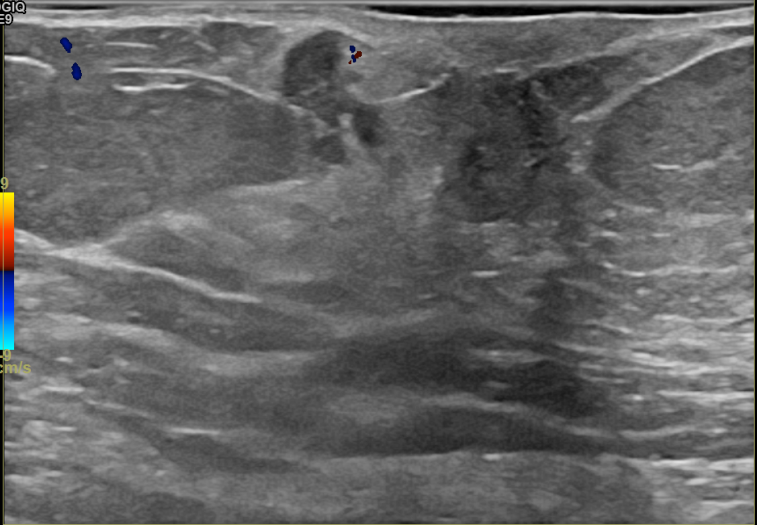

상기환자는 만져지는 멍울로 내원하신 80대초반

여성분으로 의심스러운 우측혹 조직검사 시행해 침윤성암으로 진단되었습니다